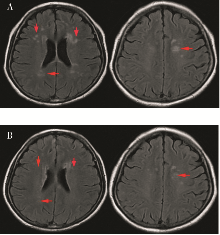

神经精神狼疮是系统性红斑狼疮严重并发症,尤其是累及中枢神经系统时,死亡率明显增加,且目前尚无标准治疗方案。本文报道1例以精神行为异常、谵语为主要表现的神经精神狼疮患者,予以利妥昔单抗序贯贝利木单抗治疗后患者症状缓解,实验室及影像学指标明显改善,为神经精神狼疮的治疗提供了新策略。

CHEN Xue, SUN Mingfang, DAI Huanzi. A case of neuropsychiatric lupus successfully treated with sequential therapy of rituximab and belimumab therapy[J]. Journal of Internal Medicine Concepts & Practice, 2025, 20(04): 316-318.